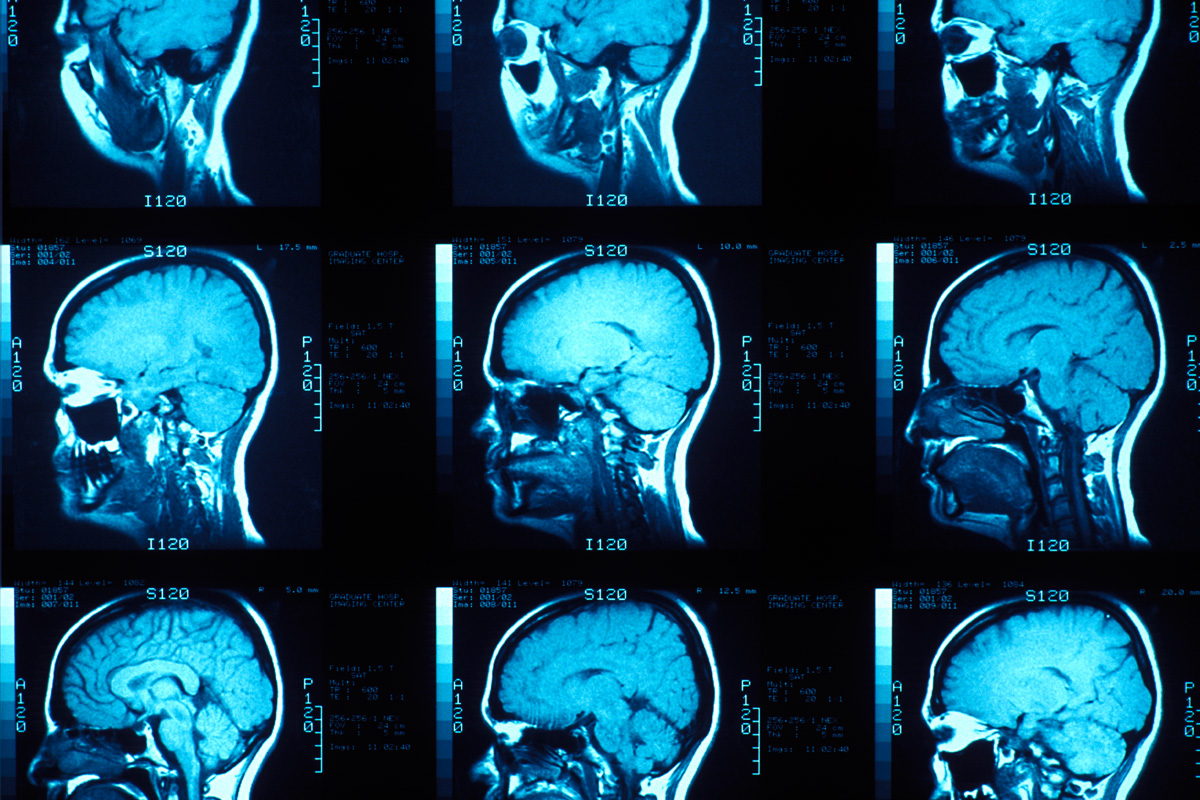

4. Causes

The cause of bipolar disorder is unknown; however, doctors believe it is due to a combination of environmental, genetic and biochemical factors. Chemical messengers in the brain called neurotransmitters associated with bipolar disorder include norepinephrine, serotonin, and dopamine, otherwise known as the “feel good” hormones. Several chromosomes have been linked to bipolar disorder, and research indicates that genetic factors may also increase the risk. Environmental factors such as life stress or emotional trauma may also play a role.